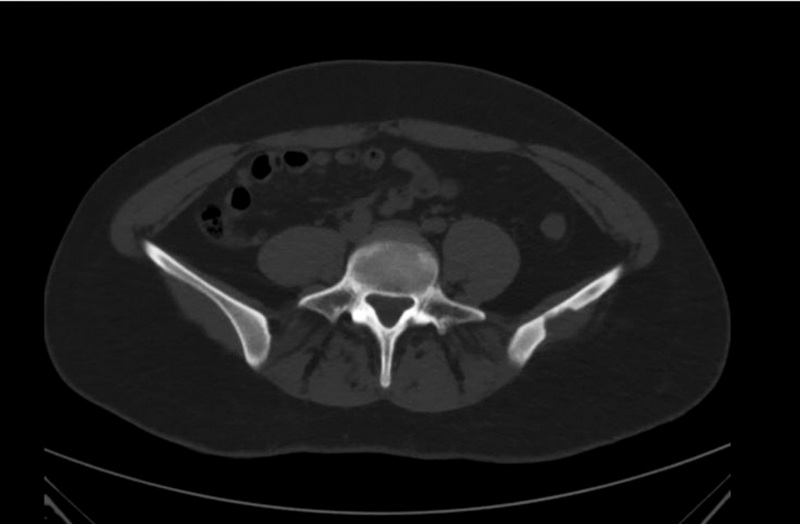

2例证实的孤立性嗜酸性肉芽肿 CT、MRI和18F-FDG PET/CT成像

本文介绍计算机诊断嗜酸性骨肉芽肿、磁共振和18F氟脱氧葡萄糖正电子发射断层扫描以及计算机断层扫描的两个临床观察。根据综合的放射学诊断研究和组织学证实,确诊为孤立性嗜酸性肉芽肿,两例患者都因怀疑原发性恶性骨肿瘤而入院。孤立性嗜酸性肉芽肿是一种相当罕见的疾病(不到1%的骨骼肿瘤体积形成病例)。最常见的是,嗜酸性肉芽肿见于头骨的顶骨和额骨,是一种溶骨体积的形成,逐渐增大。虽然大多数骨肿瘤可以通过X线摄影发现,计算机体层摄影术是首选,主要是因为它能很好地显示骨皮质层的破坏情况。计算机断层扫描和磁共振成像的诊断准确性可能不同。辐射和放射性核素诊断方法的复杂应用使能够缩小鉴别诊断的范围。在大多数病例中,现有的放射学诊断研究的特异性较低,不能做出准确的诊断,选择的方法仍然是活检后进行病理形态学检查。这些临床观察表明,当发现孤立的溶骨性病灶时,鉴别诊断需要包括嗜酸性肉芽肿。